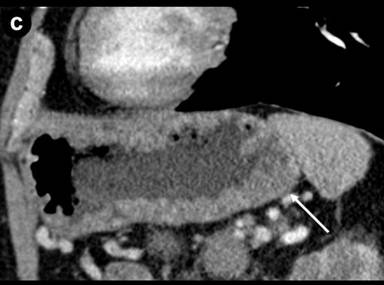

The patient was referred to our institution for consultation where he underwent repeat multiplanar MDCT with the use of 100 mL intravenous (iopromide; Ultravist® 300, Bayer, NJ, USA) contrast material delivered at 3 mL/s and imaged with a 70 s delay. Nine hundred mL oral (water) contrast was also utilized. Images were obtained at 120 kVp and 200 mAs and reconstructed at 5 mm. The pancreas was universally enlarged with a distinct rim of hypoattenuation (Figure 1). The wall of the gastric body and fundus, predominantly posteriorly, was diffusely thickened, measuring up to 1.4 cm, and had a nodular appearance (Figure 1). The gastric wall thickening spared the antrum. No hyperenhancement of the gastric wall was noted. There were additionally noted several hypodense lesions in both kidneys that were surrounded by hypovascular soft tissue (Figure 1) as well as focal jejunal wall thickening without hyperenhancement (Figure 1).

Figure 1. a. Axial MDCT image of the abdomen with intravenous and oral contrast demonstrates a thickened, “sausage-like” pancreas with a hypodense rim of tissue (arrow). b. Axial MDCT image of the abdomen with intravenous and oral contrast demonstrates a thickened and nodular appearance of the stomach wall at the level of the gastric body measuring up to 1.4 cm (arrow). c. Sagittally reformatted MDCT image of the abdomen shows the thickened and nodular gastric body wall, most pronounced posteriorly (arrow). d. Axial MDCT image demonstrates bilateral renal lesions (arrows) with a soft tissue attenuation within and immediately adjacent to the left kidney (dotted arrow). e. Axial MDCT image demonstrates focal jejunal wall thickening. |